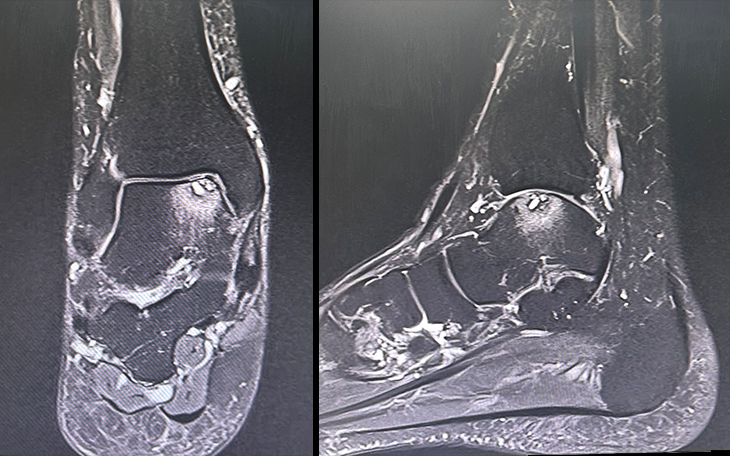

Bildquelle: www.docset.de

Symptome

Typisch sind Schmerzen im Sprunggelenk, die sich bei Belastung verstärken. Oft treten die Schmerzen auch morgens oder nach längeren Ruhephasen auf (Anlaufschmerz). Auch eine Schwellung, Steifigkeit und eine eingeschränkte Beweglichkeit des Gelenks können auftreten.

Ursachen

Häufige Ursachen sind Verletzungen (z.B. Knochenbrüche, Bänderrisse), Fehlstellungen des Fußes, Entzündungen oder auch eine genetische Veranlagung.

Konservative Therapie

Das Tragen von Schuhen mit guter Dämpfung und Unterstützung, Einlagen zur Entlastung des Gelenks, entzündungshemmende Medikamente, Physiotherapie zur Verbesserung der Beweglichkeit und Kräftigung der Muskulatur sowie Injektionen mit Kortikosteroiden oder Hyaluronsäure können die Beschwerden lindern.

Operative Therapie

Wenn die konservativen Maßnahmen nicht ausreichend helfen, können verschiedene operative Verfahren in Erwägung gezogen werden. Dazu gehören die Entfernung von Knochenanbauten (Osteophyten), die Knorpeltherapie (z.B. Mikrofrakturierung, Knorpelzelltransplantation), die Korrektur von Fehlstellungen oder die Versteifung des Sprunggelenks (Arthrodese). In bestimmten Fällen kann auch ein künstliches Sprunggelenk (Endoprothese) in Erwägung gezogen werden.